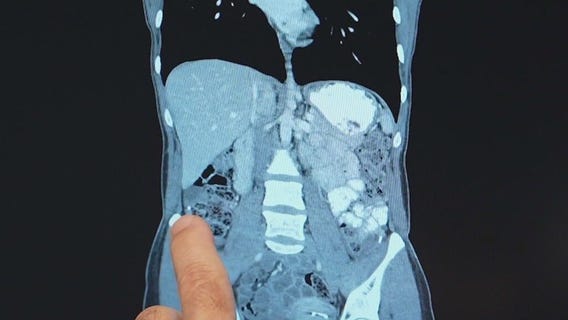

Chicago-area mom and daughter share rare heart surgery bond ahead of Mother's Day

Justine Felitto thought it was stress, but it turned out to be a life-threatening heart condition.